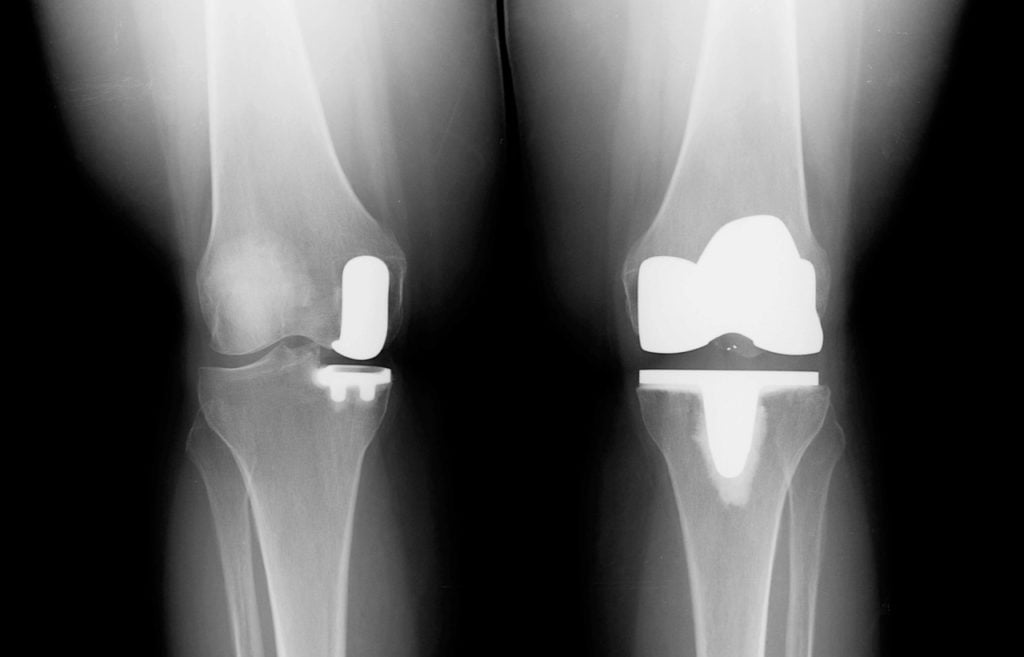

- Эндопротезирование. Наиболее эффективная и распространенная операция при гонартрозе. Пораженный сустав полностью удаляется, на его место устанавливается искусственный аналог.

Несмотря на все плюсы эндопротезирования, могут развиться и опасные осложнения (некроз, инфекция, тромбоз и т. п.). Процедура имеет ряд противопоказаний.